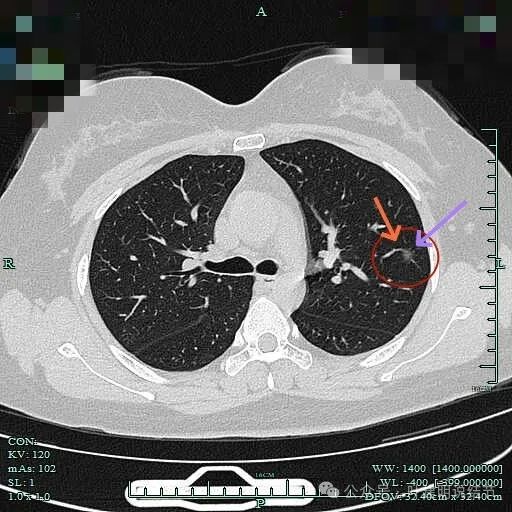

病灶小却边缘毛糙有毛刺,也见血管穿行的样子,表面不平,整体轮廓清。

见明显血管进入以及血管穿行于病灶内,边缘有细毛刺征,整体轮廓较为清楚。